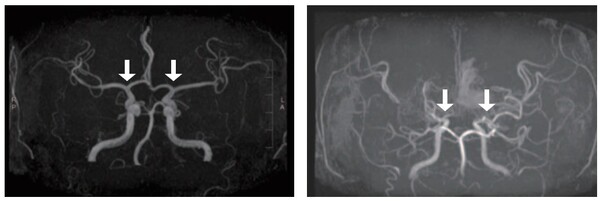

[사진 왼쪽부터] 정상 및 모야모야병 환자의 뇌혈관 |

[라포르시안] 희귀난치성 뇌혈관질환 '소아 모야모야병'의 발생 양상과 치료 및 예후를 전국 단위로 분석한 결과가 나왔다.